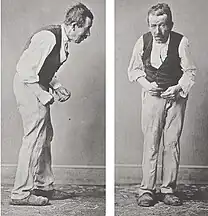

A. 1880s illustration of Parkinson’s disease (PD) B. Mild motor-predominant PD C. Intermediate PD D. Diffuse malignant PD | |

An illustration of advanced Parkinson's disease by William Richard Gowers was published in 1886 in A Manual of Diseases of the Nervous System, based on 1879 photographs attributed to Albert Londe.[164][165] A new image was created in 2020 to represent diversity in levels of severity.[176][177]